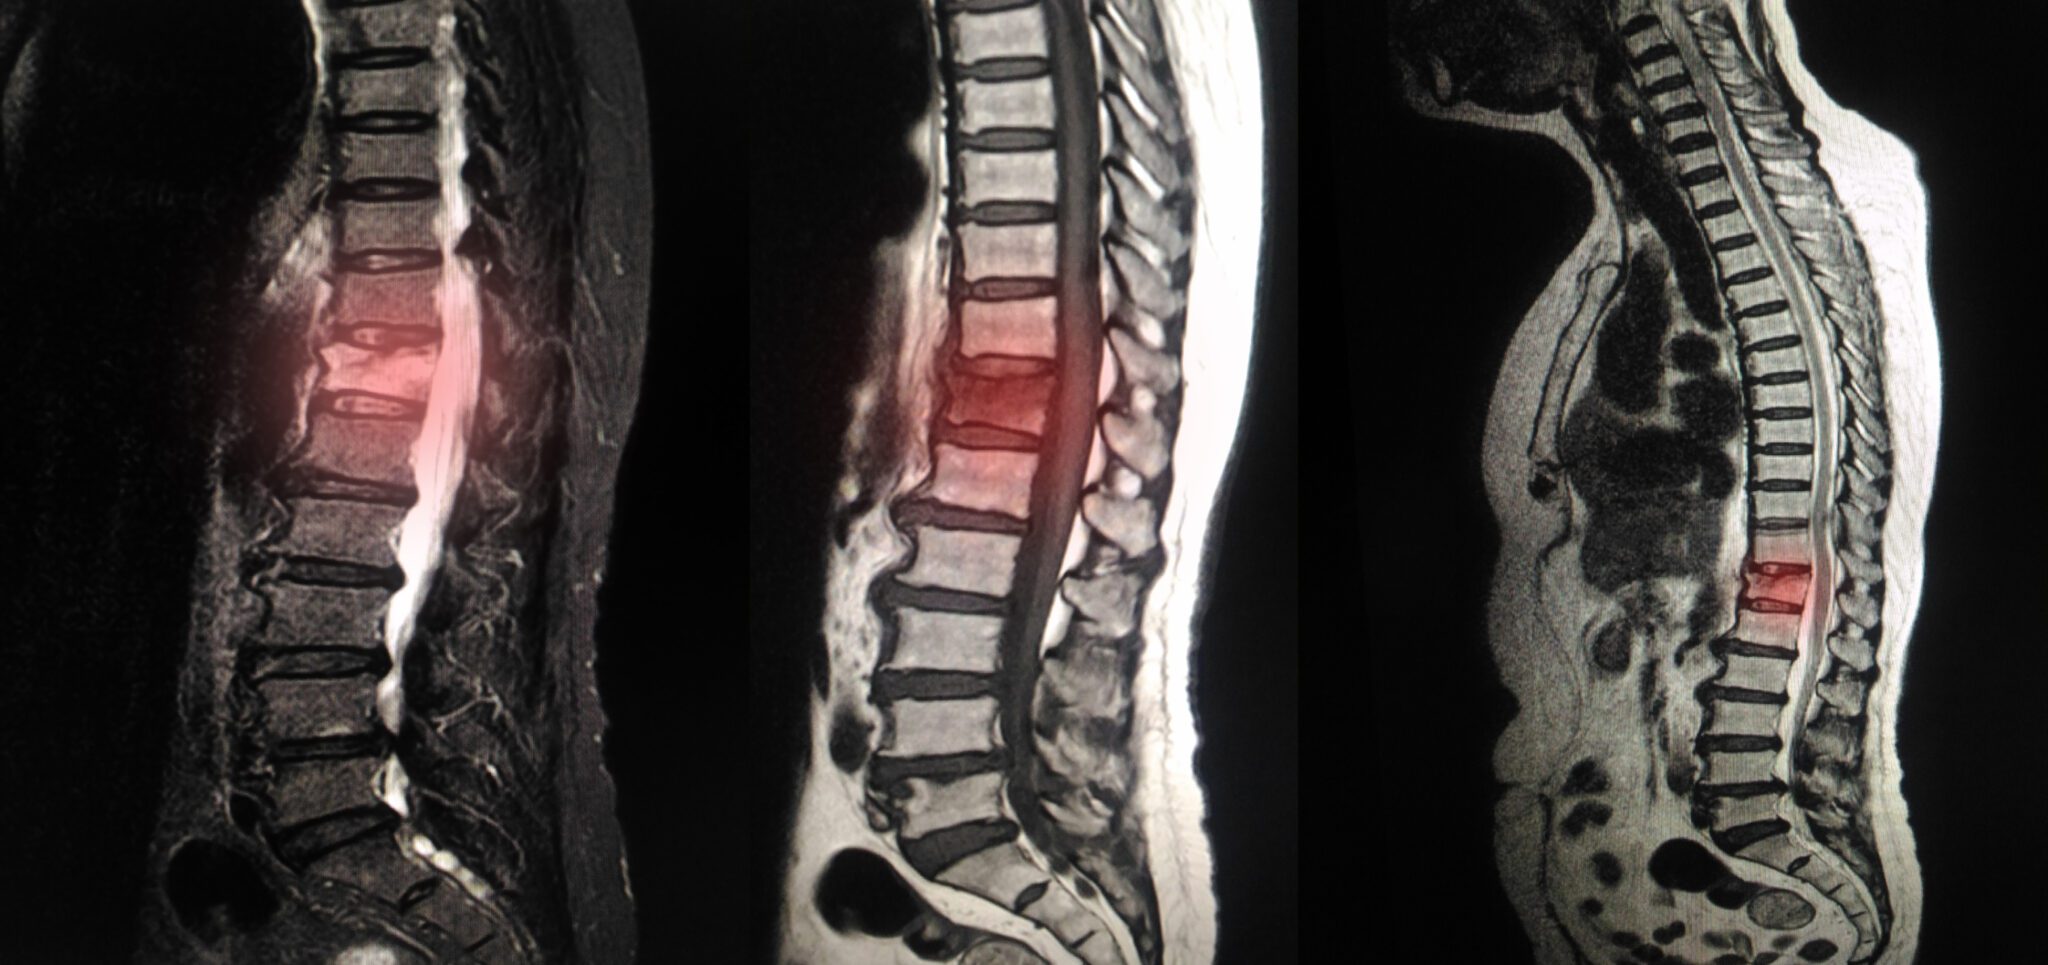

Disc Clinic BC Vancouver BC Degenerative Disc Treatment

Disc Clinic BC Vancouver BC Degenerative Disc Treatment Degenerative Arthritis Disability Web osteoarthritis causes pain and stiffness in the joints for many people as they get older; The symptoms of degenerative arthritis will. Joint pain and stiffness can become. Web applying for disability benefits for arthritis can be a long grueling process, but patience and persistence can pay off. In severe cases, you may be unable to perform daily tasks or.. Degenerative Arthritis Disability.